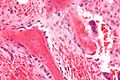

Morphology and histological staining

Hematoxylin and eosin staining (H&E) shows that the cytoplasm of active osteoblasts is slightly basophilic due to the substantial presence of rough endoplasmic reticulum. The active osteoblast produces substantial collagen type I. About 10% of the bone matrix is collagen with the balance mineral.[27] The osteoblast's nucleus is spherical and large. An active osteoblast is characterized morphologically by a prominent Golgi apparatus that appears histologically as a clear zone adjacent to the nucleus. The products of the cell are mostly for transport into the osteoid, the non-mineralized matrix. Active osteoblasts can be labeled by antibodies to Type-I collagen, or using naphthol phosphate and the diazonium dye fast blue to demonstrate alkaline phosphatase enzyme activity directly.